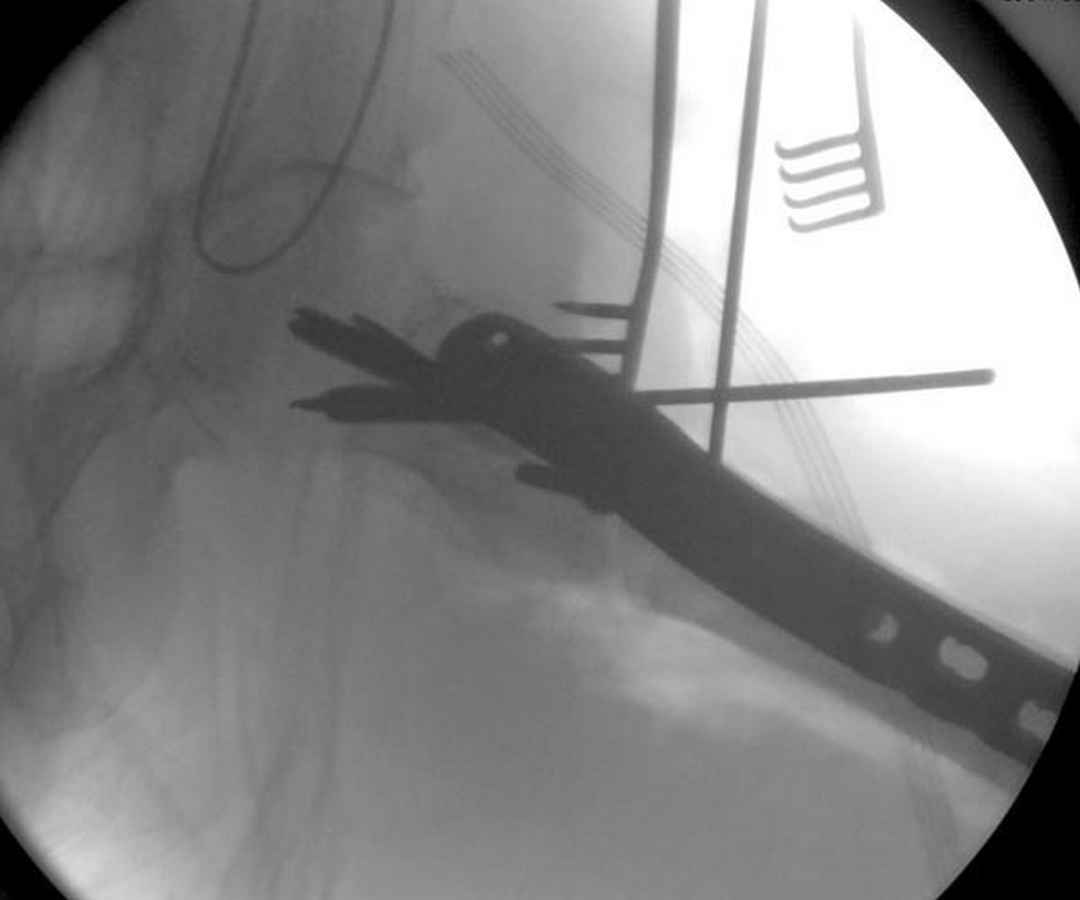

Здесь пара случаев фиксации похожих переломов:

первый высокоэнергетическая травма 36 лет

Здесь 83 года, травма в результате падения

судя по картинкам с ЭОПа явно использовались приемы непрямой репозиции под его контролем, а так же интраоперационный ЭОП-контроль положения винтов, без такого контроля операция может ухудшить ситуацию (опять же учтите сроки) т.к. результат буде зависеть в большей степени от искусства хирурга, а не от технологии